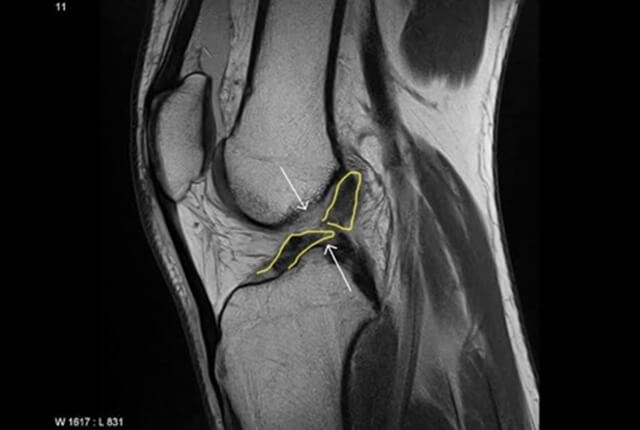

• MRIでACL損傷や半月板損傷を確定診断

診断2

半月板の断裂形態

• 縦断裂

• 横断裂

• 水平断裂

• フラップ状断裂

• バケツ柄状断裂

• 変性断裂